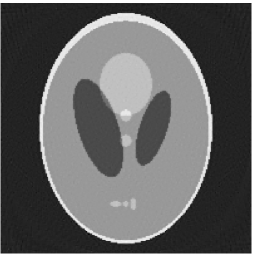

Noiseless projection data: The projection data were collected by calculating line integrals across the phantom at 60, 90, 120 directions(equal increments and from to ) of 201 equally spaced parallel lines from to . Iteration procedures were terminated when for the noiseless experiments.

The reconstruction images from the noiseless projection data were shown in the Fig. 2. From Fig. 2, we can observe that the classic and the proposed algorithms can reconstruct images from the three projection data. In order to show the advantages of the proposed algorithm visually, the central vertical line of the differences between the reconstructed images and the original image are present in Fig. 3. We can observe that the -PP superiorization is more efficient than the classic superiorization in the aspect of suppressing the artifacts in the reconstructed images.

In order to compare the images in Fig. 2 quantitatively, we tabulated the iterations, MSE, Res and running time(RT) of programs in Table 1. By comparing the numbers in Table 1, we can draw the conclusion that the proposed method can improve the quality of the estimated images and save computation time.

In order to compare the convergent speed of the proposed algorithms with the classic algorithms visually, we present the evolution of MSE along with the iteration process in Fig. 4 for the 3 projection data. And we can observe that the proposed perturbation can accelerate the convergent rate and improve the reconstructed image qualities.

In summary, the proposed superiorization algorithm has faster reconstruction speed than the classic superiorization algorithms, and the MSEs of the reconstruction images by the proposed algorithm are smaller than these of the reconstructed images by the classic superiorization algorithm regardless noiseless and noised projection data. Therefore, the above results demonstrate that the modified superiorization algorithm can accelerate the convergent speed and improve the image qualities.